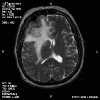

Radiology of the case:

T1-weighed MR images demonstrate an extraaxial, dural based mass involving the right supraorbital region  (Panel A and B). The mass shows homogeneous enhancement  (Panel C). CT scan demonstrates as well as rim calcification (Panel E). On T2-weighed imagers, significant vasogenic edema is demonstrated despite the small size of the lesion and the extraaxial location (Panel D).